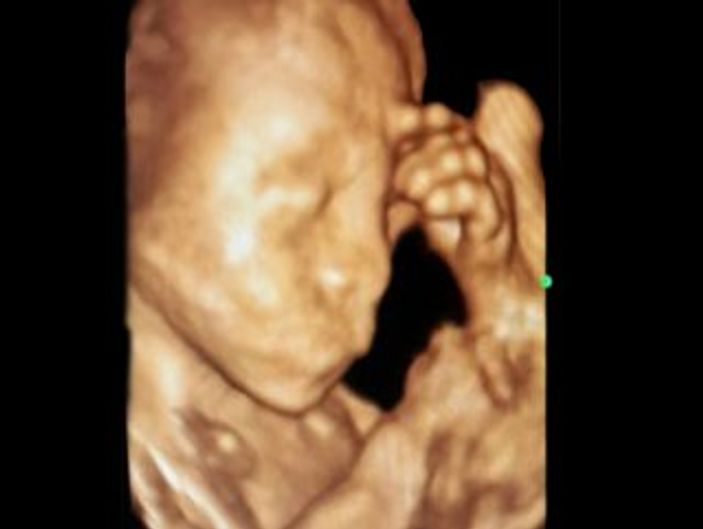

Konya’da 23 haftalık bebeğinin anne karnında elini başına koyarak düşünen hali ultrason ile kaydedildi.

Konya’nın Ereğli ilçesinde bir anne adayının kontrol edilen 23 haftalık kız bebeği 4 boyutlu ultrason cihazında elini başına koyarak düşünürken görüldü. Gördüğü manzara karşısında şaşıran Kadın Doğum Uzmanı Op. Dr. Kadriye Turgut bu anı ölümsüzleştirerek fotoğraf olarak kaydetti.